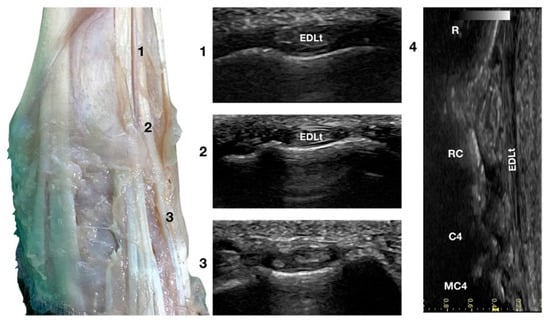

3.1.3. Extensor Digitorum Lateralis Tendon (EDLt) Ultrasonographic Anatomy

Just lateral to the EDCt at the ulnar notch of the radius, on a transverse scan, the Extensor Digitorum Lateralis tendon (EDLt) was seen as a small, oval to slightly rounded shaped structure (Figure 1a). It was more dorsomedially located than the more prominent Extensor Carpi Ulnaris tendon (ECUt), easily palpated on the lateral face of the carpus. It was the only tendinous structure lateral to the EDCt and medial to the ECUt. Proximally, the tendon maintained the same size and shape until the tenomuscular junction. Distally, at the intercarpal joint level, the homogeneous echogenicity of the tendon was interrupted by an oblique hyperechoic line that demarcated the two components arising from the united tendon (Figure 4).

Figure 4.

Dorsal carpal face centred on the Extensor Digitorum Lateralis tendon. At the ulnar notch level (2), the EDLt is seen as a thin oval tendon embedded in the deep Extensor Lateralis groove. Proximally (1), the tendon is thicker. The EDLt divides into two parts distally at the intercarpal joint (3). On the longitudinal scan plane (4), the fine fibrillar pattern of the thin medial tendon is visible. The bony surface beneath is recognisable. R, radius; RC, radiocarpal bone; C4, carpal bone four; MC4, fourth metacarpal bone.

The two parts of the EDLt passed through the groove between the distal ends of the radius and the ulna, over the dorsolateral border of the carpus to the metacarpus, and then diverged from each other. The two thin tendons (the medial is the smaller) passed over the dorsolateral surface of the corresponding metacarpal bones (third and fourth for the medial tendon, and the ulnar carpal bone for the lateral tendon). They ended on the dorsal surface to the distal phalanges of digits III, IV (the medial tendon divided into two branches), and V (the lateral branch). They were surrounded by a thick hyperechoic line (fibrous tendon sheath). The tendons, even if thin, were seen in the longitudinal scan until the mid-metacarpal diaphysis. It is possible that, in larger breed dogs, the tendon can be evaluated more distally. Elevating the foot from the ground and rotating the probe to check the longitudinal scan plane often helped in examining the distal portion. The extension and flexion of the lateral digits helped to better differentiate the tendon from the surrounding tissues and assess tendon function, lesions, adhesion, and subluxation.